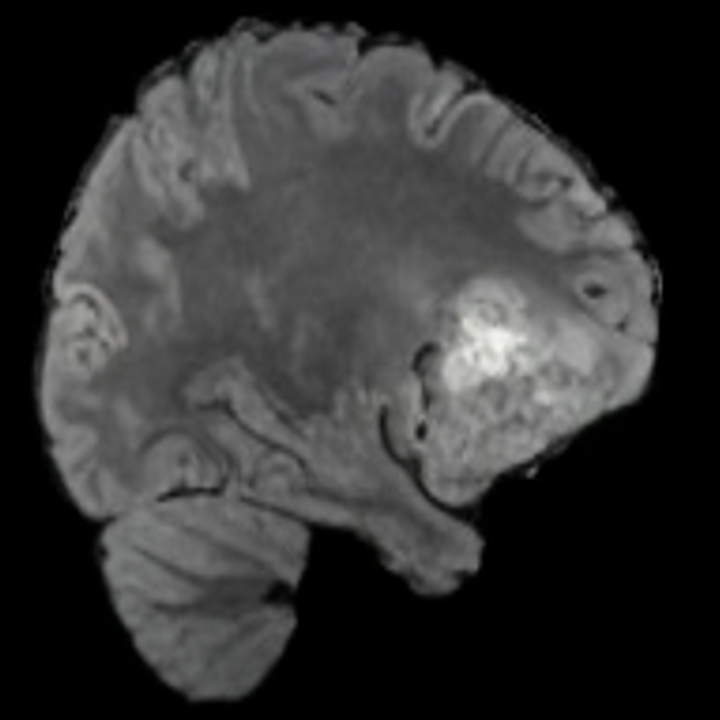

Tumour Information Preservation. For the brain tumor segmentation, we use a Swin UNETR model[28, 70], trained with random rotation, and intensity as data augmentation. On the test set with human ground-truth annotations (), the brain volumes generated from single slice input preserve the volume of the different tumour components (paired t-test, for all 3 classes). In Figure 4, we highlight the tumor profiles of the generated MRIs compared to the ground truth tumour profile. The real MRI Dice score in the test set is 85.15 while the generated MRIs from a single slice have a dice score of 83.09. This shows how the generated MRIs indeed preserve the tumor information and can act as an affordable and informative pseudo-MRI, before conducting an actual costly MRI examination in hospitals. More detailed results are provided in supplementary material.

Leveraging Context. Since we train on a predominantly cancerous brain dataset, one question that might arise is whether X-Diffusion generated MRIs preserve tumour information when the given inputs do not intersect with any tumour. We perform experiments varying the input slice index used to generate the 3D brain MRIs and measure the performance for input slices with no intersection with the tumour (not a single pixel with tumor label in the input slice). We also measure performance when only input slices are selected from tumor range. The Dice Scores of the random slices, no-tumour, and only-tumour are 83.09, 79.23, and 83.68 respectively. As can be seen here, the brain volumes generated from input slices with no tumour still preserve tumour information in reconstructed brain volumes despite a small drop in performance. This indicates that X-Diffusion is leveraging the context to preserve key information, such as tumor locations. This observation is consistent with how tumor segmentation models with global context [13] perform better than local-based U-Nets. More details are provided in supplementary material.